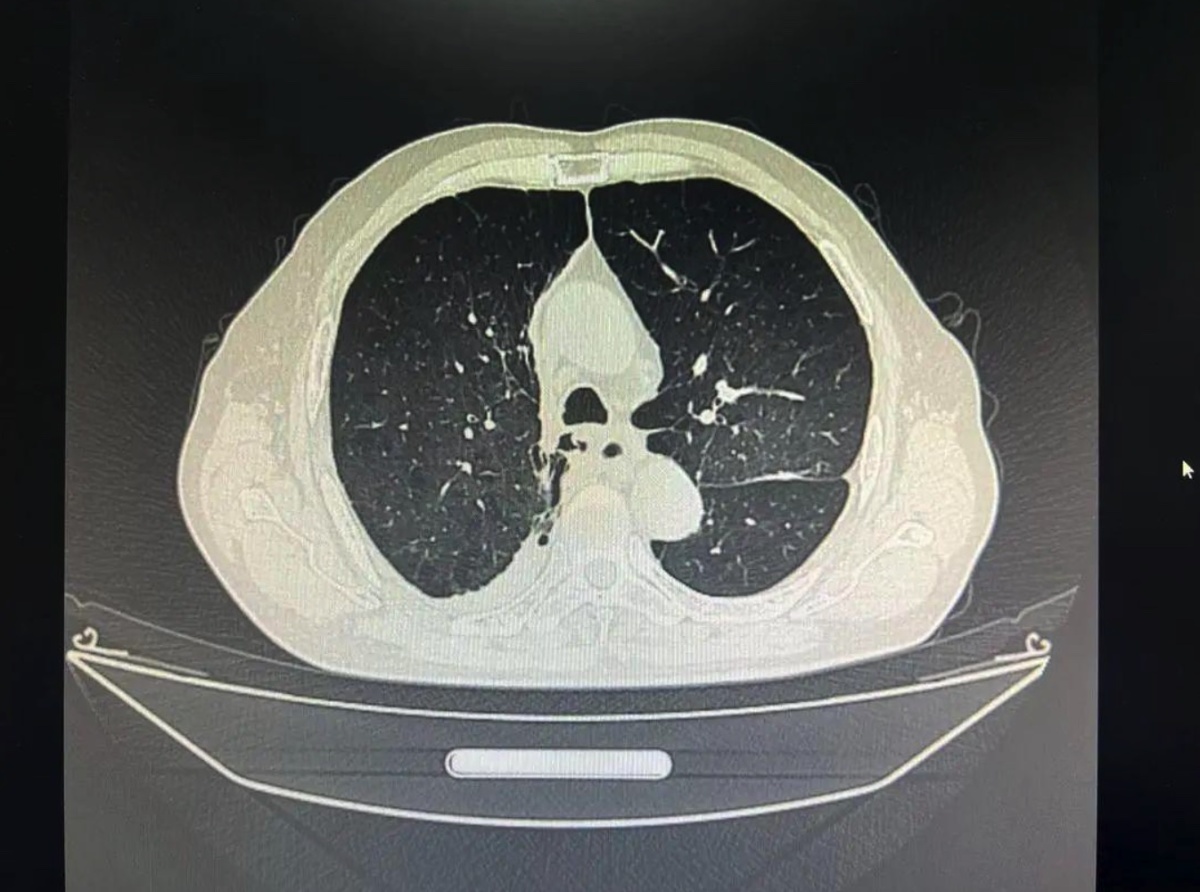

看着父亲痛苦的样子,王峰国的儿子焦虑不已。父亲为这个大家庭操劳了一辈子,到老了该享清福了,身体却不行了。他拿着父亲的片子走遍当地各大医院,医生均告诉他,他父亲的肺气肿太严重了,右肺已经完全变成一个巨大的肺大泡,填满了整个右侧胸腔,导致右肺没有一点呼吸功能,而且他左肺肺气肿也不轻,所以才会闷成这样,想要治好,除非做肺移植。

无法行动的王峰国由救护车送至河南省胸科医院,住院后,乔亚红对王峰国的胸部CT进行三维重建,发现王峰国右肺除了有一巨型大泡,右肺底还有一点点的肺不张,应该是正常的肺组织被巨大的大泡压缩所致,如果把大泡去掉,这些肺组织便可复张恢复呼吸的功能,能大大提高他的肺功能,闷气也有望改善。

△王峰国的肺大泡处于游离状态

手术后的王峰国不闷气了,伴随多年的哮鸣音也消失了,术后复查胸部CT可见右肺复张,他自己也能下床走动,活动自如了,脸上露出了久违的笑容。